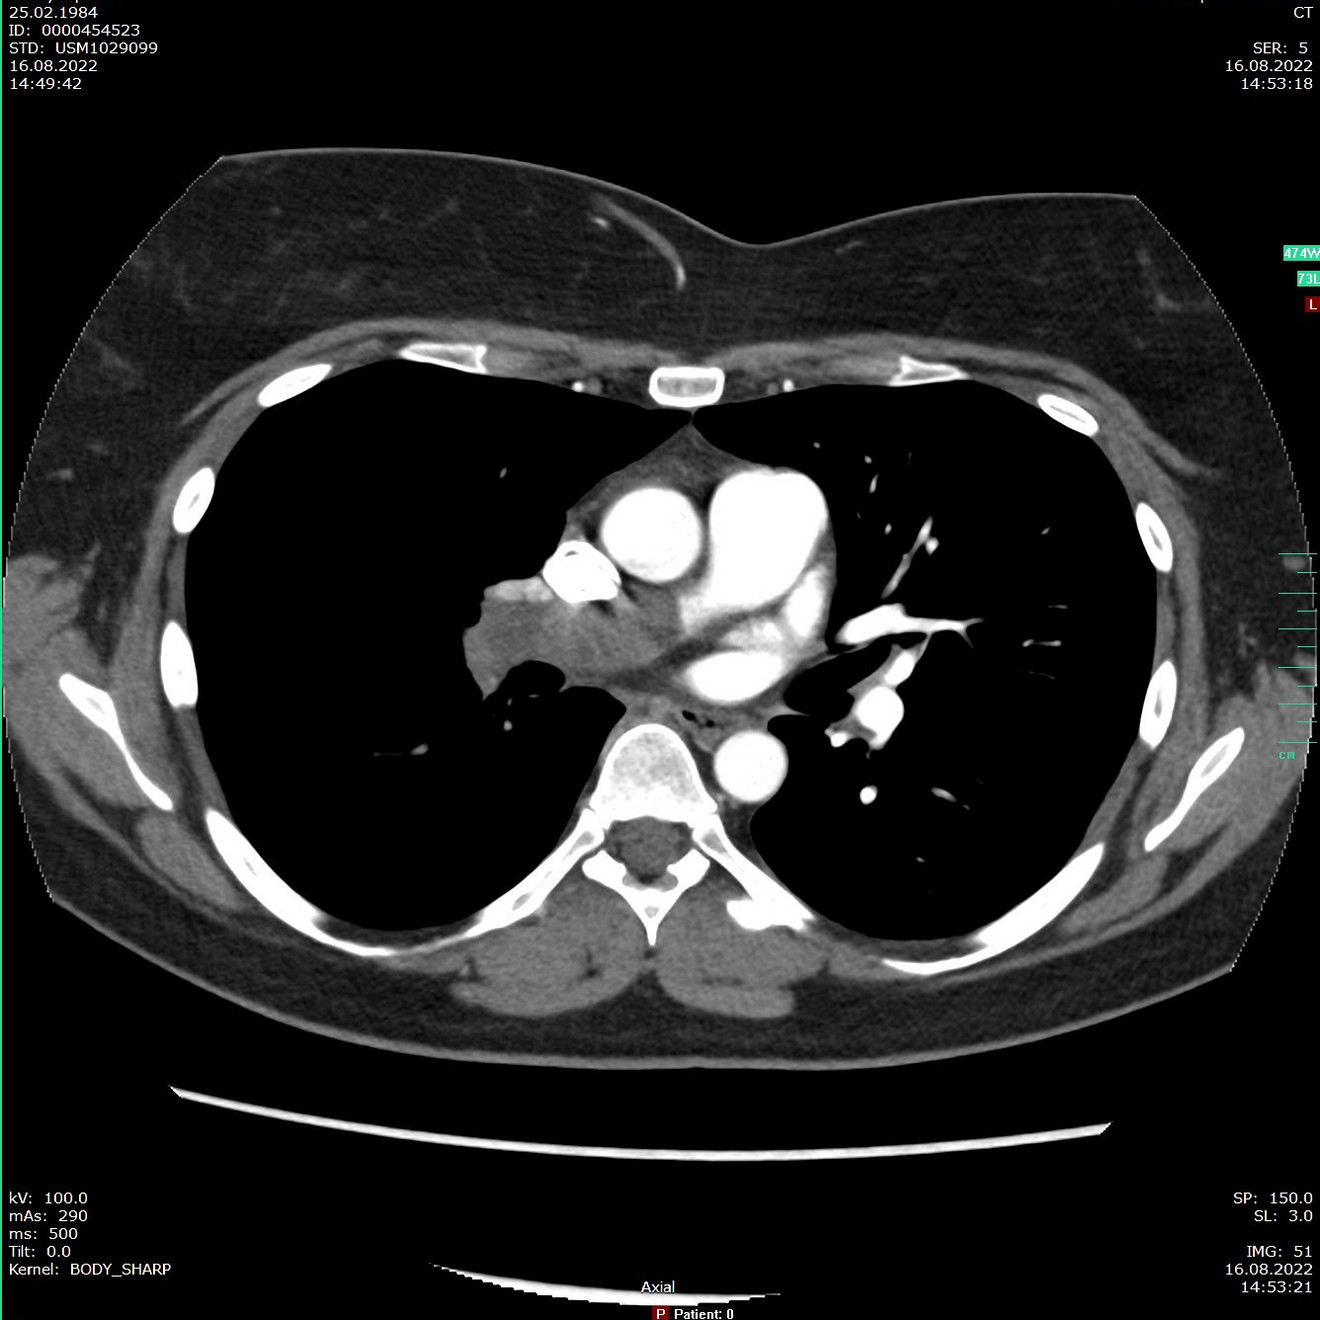

Die Lungenembolie ist nach Herzinfarkt und Schlaganfall die dritthäufigste zum Tode führende Herz-Kreislauf-Erkrankung. Bei einer Lungenembolie führt ein Thrombus, umgangssprachlich auch als Blutgerinnsel bezeichnet, zu einem vollständigen oder teilweisen Verschluss von Lungengefäßen. Die lebensgefährlichen Blutgerinnsel entstehen meistens in den tiefen Beinvenen. Wichtige Anzeichen sind beispielsweise Schmerzen, Schwellungen sowie eine bläuliche Verfärbung der Haut. In einigen Fällen bleibt eine Thrombose unbemerkt.

Die Ursachen sind in den meisten Fällen Veränderungen der Blutzusammensetzung und der Blutströme. Aber auch entzündliche Prozesse im Venensystem können die Entstehung von Thromben begünstigen. Eine Thrombose bildet sich oft nach einer längeren Unbeweglichkeit des Körpers wie einer Bettlägerigkeit oder einer langen Auto- oder Flugreise. Löst sich ein Thrombus, gelangt er durch die Venen über das Herz in die Lungen-

gefäße. Durch den geringeren Durchmesser der Lungenarterien setzt sich der Embolus, so bezeichnen Mediziner einen abgegangenen Thrombus, fest und verhindert den Sauerstoffaustausch der nachfolgenden Lungenareale.